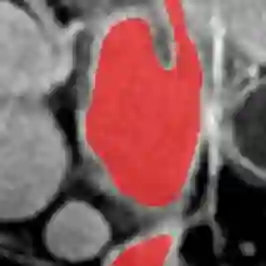

Medical data often exhibits long-tail distributions with heavy class imbalance, which naturally leads to difficulty in classifying the minority classes (i.e., boundary regions or rare objects). Recent work has significantly improved semi-supervised medical image segmentation in long-tailed scenarios by equipping them with unsupervised contrastive criteria. However, it remains unclear how well they will perform in the labeled portion of data where class distribution is also highly imbalanced. In this work, we present ACTION++, an improved contrastive learning framework with adaptive anatomical contrast for semi-supervised medical segmentation. Specifically, we propose an adaptive supervised contrastive loss, where we first compute the optimal locations of class centers uniformly distributed on the embedding space (i.e., off-line), and then perform online contrastive matching training by encouraging different class features to adaptively match these distinct and uniformly distributed class centers. Moreover, we argue that blindly adopting a constant temperature $\tau$ in the contrastive loss on long-tailed medical data is not optimal, and propose to use a dynamic $\tau$ via a simple cosine schedule to yield better separation between majority and minority classes. Empirically, we evaluate ACTION++ on ACDC and LA benchmarks and show that it achieves state-of-the-art across two semi-supervised settings. Theoretically, we analyze the performance of adaptive anatomical contrast and confirm its superiority in label efficiency.

翻译:医学数据经常呈现长尾分布和重度类别不平衡,这自然导致在对少数类别(即边界区域或罕见目标)进行分类时出现困难。最近的研究在长尾情况下通过装备医学影像的无监督对比标准,明显改进了半监督医学图像分割。然而,在标记的数据部分中,类别分布也极为不平衡,因此它们的表现如何仍不清楚。在本研究中,我们介绍一种采用自适应解剖对比度改进的对半监督医学分割行动的框架(ACTION++)。具体来说,我们提出了一种自适应监督对比损失,它首先在嵌入空间上计算出不同类别的优化位置(即离线),然后通过鼓励不同类别之间的特征与这些不同和均匀分布的类别中心相适应的在线对比匹配训练来进行自适应匹配。此外,我们认为,在长尾医疗数据中盲目采用常温度$\tau$不是最优的,因此通过一个简单的余弦计划来使用动态$\tau$来产生更好的多数类别和少数类别之间的分离。在实证方面,我们在ACDC和LA基准测试中评估ACTION++,并展示了其在两种半监督设置下的最新成果。从理论上讲,我们分析了自适应解剖对比度的性能,并证实了它在标签效率上的优越性。